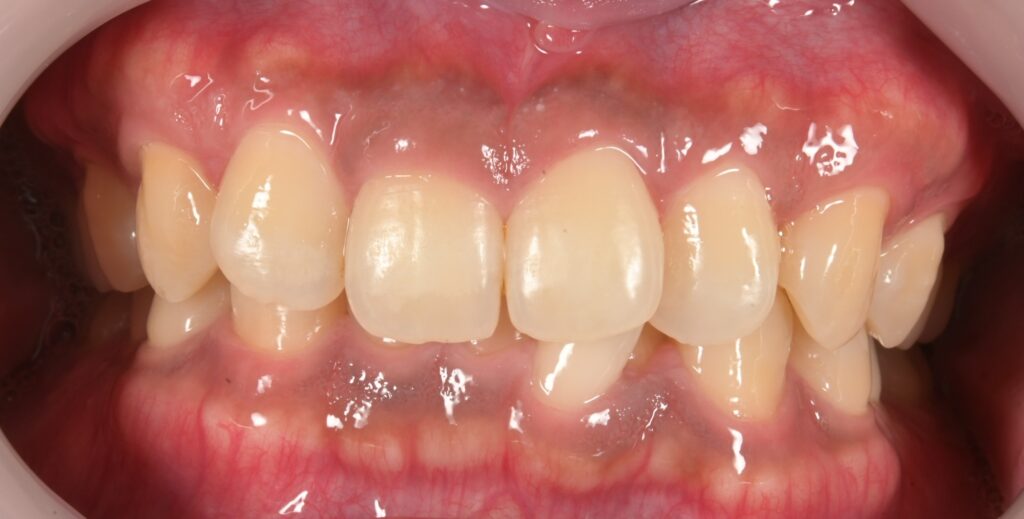

【27歳女性】7ヶ月で前歯の歯並びが改善✨マウスピース矯正(iGO)で手に入れた理想の笑顔

こんにちは!しんデンタルクリニックです🍀 心地よい春風が吹く季節になりましたが、皆様いかがお過ごしでしょうか。今回は「前歯の歯並びが気…more